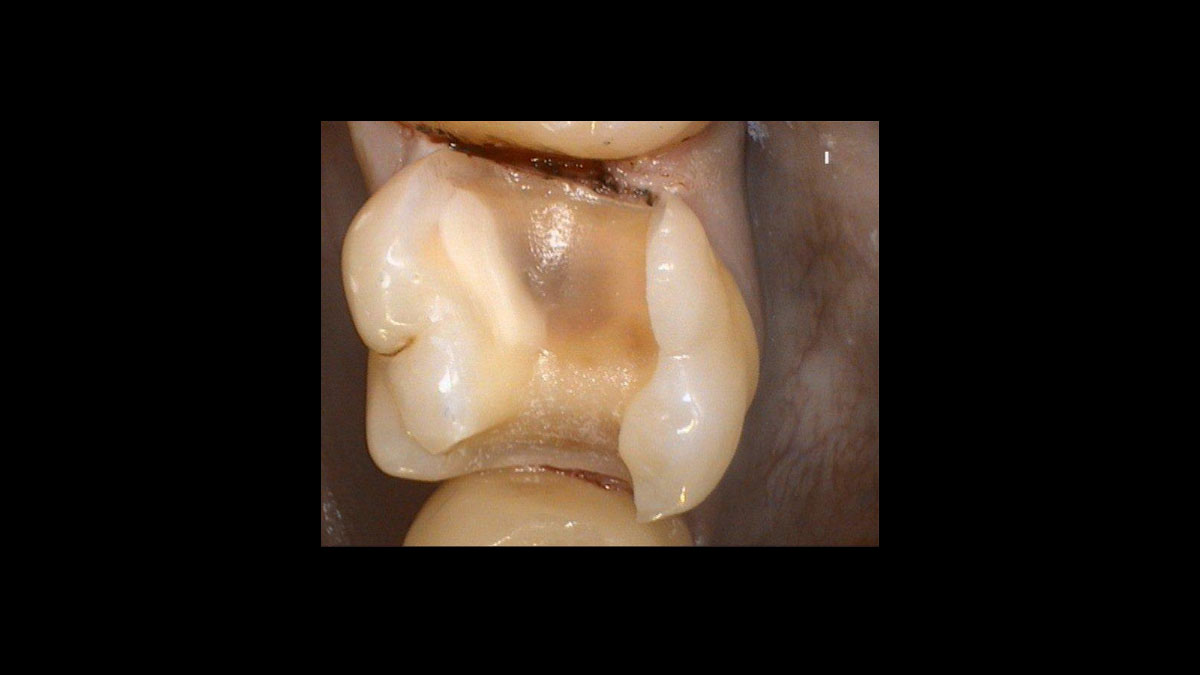

• Exposing a displaced tooth (no predefined treatment program)

Exposure of a displaced tooth